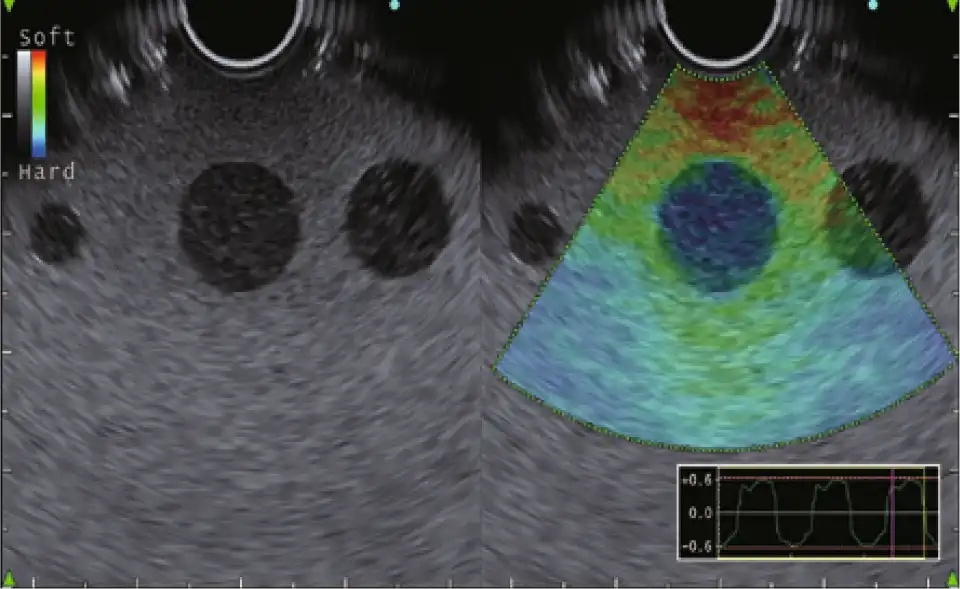

改进的弹性成像

EU-ME3 具有弹性成像功能,在压缩和回缩过程中,可以看到组织的应变量(组织硬度),从而可以获得更多关于组织特性的信息。

弹性成像 (i-ELST)

i-ELST是纳入EU-ME3的一项新技术,使其更容易显示弹性图像,即使在脉动引起的位移不大。